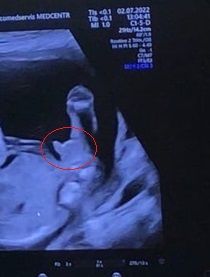

Девочки,ну мальчик же..??

1000% пацан, морковка что надо!!!)))

Мальчик

Конечно мальчик 👦 😊

Мальчик)

Ну, как-то очевидно, по-моему))

Юлия Sonnце, я просто не думала,что к 20 неделям будет так отчётливо видно)